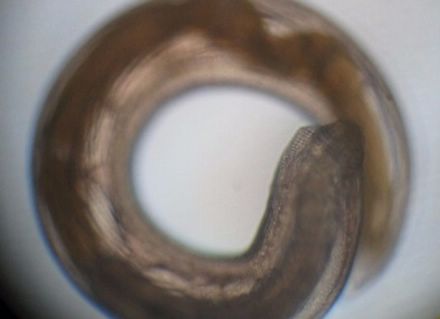

实验君把它放在解剖镜下观察。我勒个苍天!一大片蠕动的虫子!透明的表皮,黄色和白色的身体,有的展开身子像蚯蚓一样游动,有的盘起来像螺蛳一样!可以想象这些家伙在我们的胃里会是什么样!

颚口线虫

医生说,从黄鳝沉渣里挑出来的叫做颚口线虫,用肉眼看非常小,最长的可能也就几毫米,实验人员在我们买的10斤黄鳝中,找到了250条颚口线虫!而这些只是颚口线虫的幼虫,它们在黄鳝体内还会长大!

下面这只“未成熟”成虫看起来就明显大了几倍,褐色的身体,头还在转动。